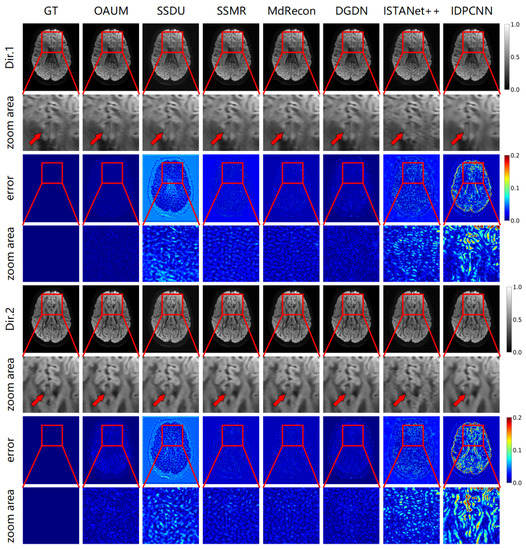

Figure 5 demonstrates the reconstruction effect of our model at a higher sampling rate. The figure shows the reconstructed DWIs of each model and its residual images compared to the true fully sampled image at an 8-fold acceleration factor (sampling rate of 0.125). Our method outperformed all other methods in detail recovery, as shown by the red arrow in the DW image. Comparing the Dir.1 and Dir.2 directions, OAUM exhibited a worse performance in the Dir.2 gradient direction than the Dir.1 direction because Dir.2 DWIs were reconstructed from q-space undersampled data. However, compared to self-supervised method SSDU and supervised methods ISTANet++ and IDPCNN, OAUM still had significantly lower errors, demonstrating its superiority.

Figure 5. The DWI results reconstructed from models with acceleration factor (AF) = 8 and two diffusion gradient directions.

Table 2 gives the quantitative evaluation results for reconstructing DW images using various methods with an 8-fold acceleration factor. The results indicate that our method is superior, while the MdRecon method is inferior under this level of sampling. Our method outperforms the suboptimal approach by achieving an 18% improvement in RMSE and a 5% increase in PSNR.